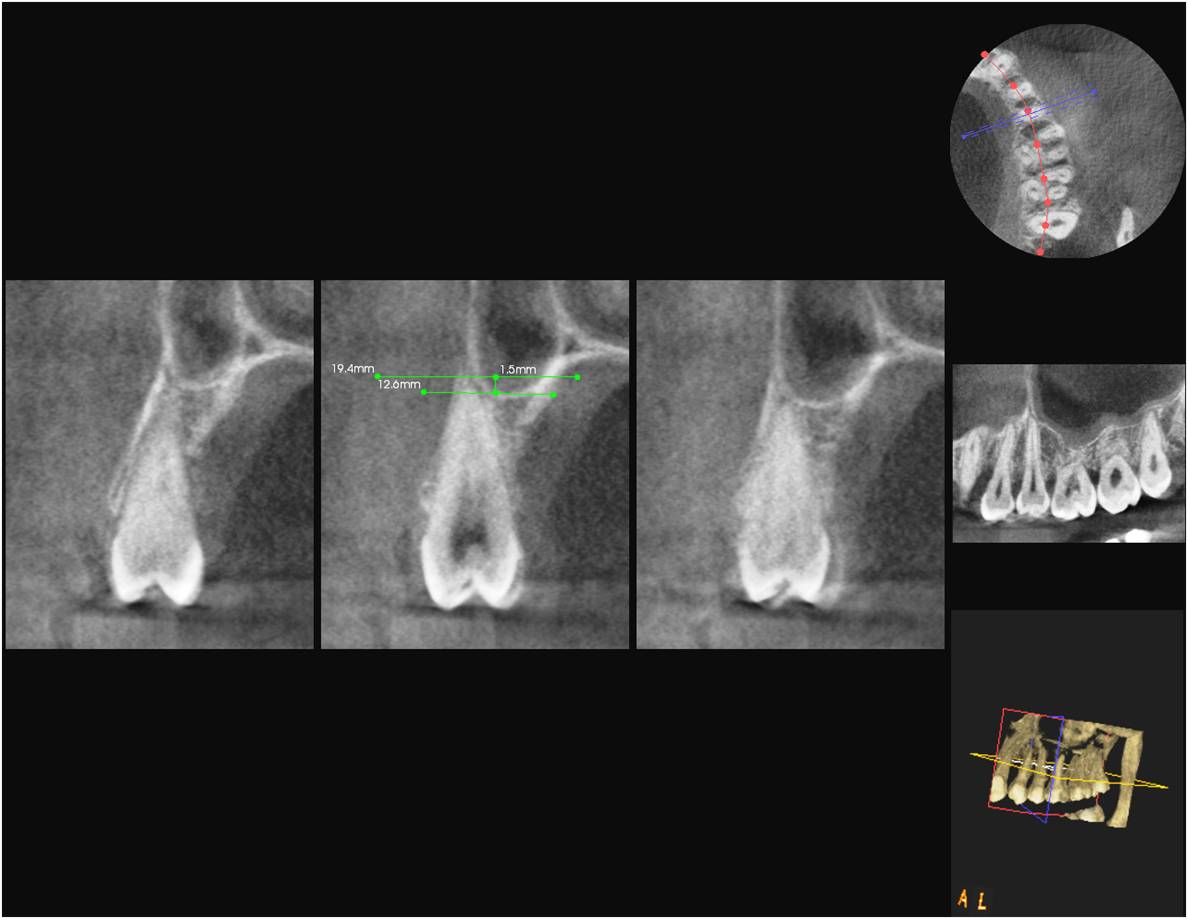

Materials and Methods: A total of 510 maxillary teeth from 85 patients were classified according to their topographic relationship to the maxillary sinus and measured according to their projection lengths on the sinus cavity using OPG and DVT modalities.

Results: In cases of classification 0, 85% and in classification 1 , 55.3% cases shows similar classification in both OPG and DVT. 28.5% of cases in both imaging modalities show classification 2. Only 15.9% of teeth roots exhibits classification 3. 11.1% of cases showed classification 4.The panoramic radiograph showed a statistically significant 2.24 times longer root projection on the sinus cavity in OPG comparison to DVT images.

Conclusion: Teeth roots projecting in to the sinus in OPG, shows no vertical protrusion in to the sinus in DVT images. Hence DVT was better than OPG with measurements that were more exact and closer to anatomical reality.